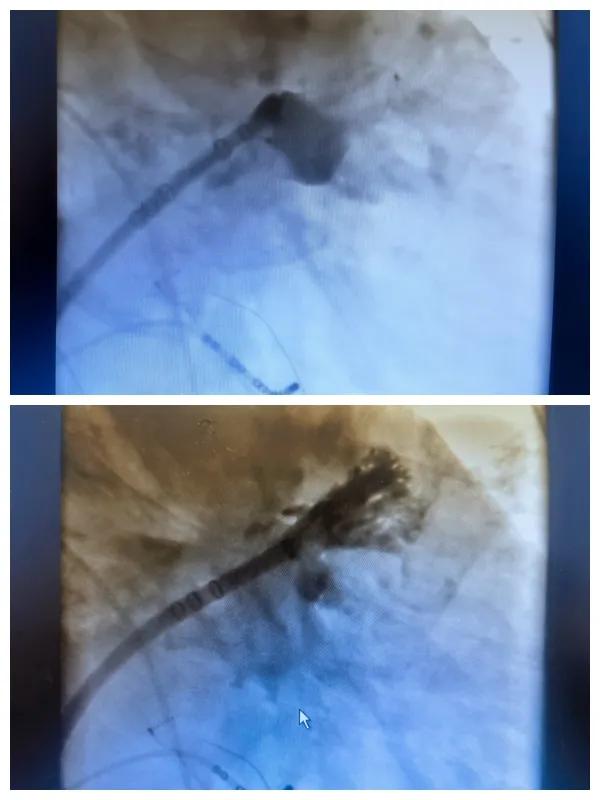

6月26日,市二院成功為一名老年房顫患者實施了房顫射頻消融術+左心耳封堵WM FLX一站式介入治療,標志著醫(yī)院在心律失常介入治療領域邁出了嶄新的一步,開啟了新的治療篇章。

本次手術特邀我國著名心血管內(nèi)科專家、河南省胸科醫(yī)院黨委書記袁義強及血管內(nèi)科七病區(qū)主任黃瓊教授蒞臨指導,市二院院長王瑾帶領心血管內(nèi)科電生理等專家團隊緊密合作,一次性解決了患者房顫、血栓兩大困擾,也使患者告別了終身服用抗凝藥的痛苦,極大地降低了患者的經(jīng)濟和用藥負擔。

為了讓患者得到全面、綜合的治療,經(jīng)過團隊術前充分討論,并征得家屬同意,心血管內(nèi)科團隊決定采用目前國內(nèi)外先進的房顫射頻消融術+左心耳封堵WM FLX一站式介入微創(chuàng)手術來治療老人的疾病。整個手術過程圓滿順利,術后何大爺各項體征正常,蘇醒后順利返回病房。